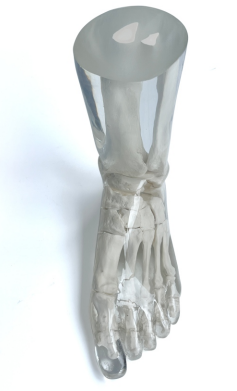

成人腿部模體,用于 X 射線 CT 和超聲波的成人腿部(肌肉)模型是一種基于人類男性腿部平均解剖結(jié)構(gòu)設(shè)計(jì)的逼真模型。它具有所有基本的骨骼和

軟組織特征,使其成為學(xué)習(xí)、研究和測試醫(yī)學(xué)成像設(shè)備的理想工具。 模體可用于研究不同方向和定位技術(shù)的多種診斷性 X 射線 CT 和超聲程序。根據(jù)

要求,該產(chǎn)品可以根據(jù)不同的病理進(jìn)行定制,也可以用于特定的培訓(xùn)應(yīng)用。 模體尺寸:965.2 x 254 x 177.8 毫米,重量:12kg(約)